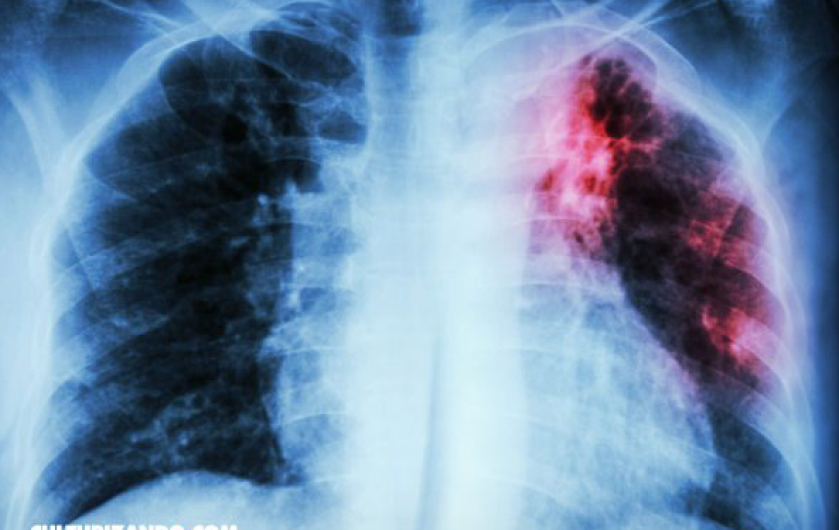

Detectan más casos de Tuberculosis en Nuevo Laredo

En lo que va del año, se han registrado un total de 48 casos nuevos de personas portadoras de Tuberculosis, de acuerdo con el departamento de Microbacteriosis de la Jurisdicción Sanitaria 5.